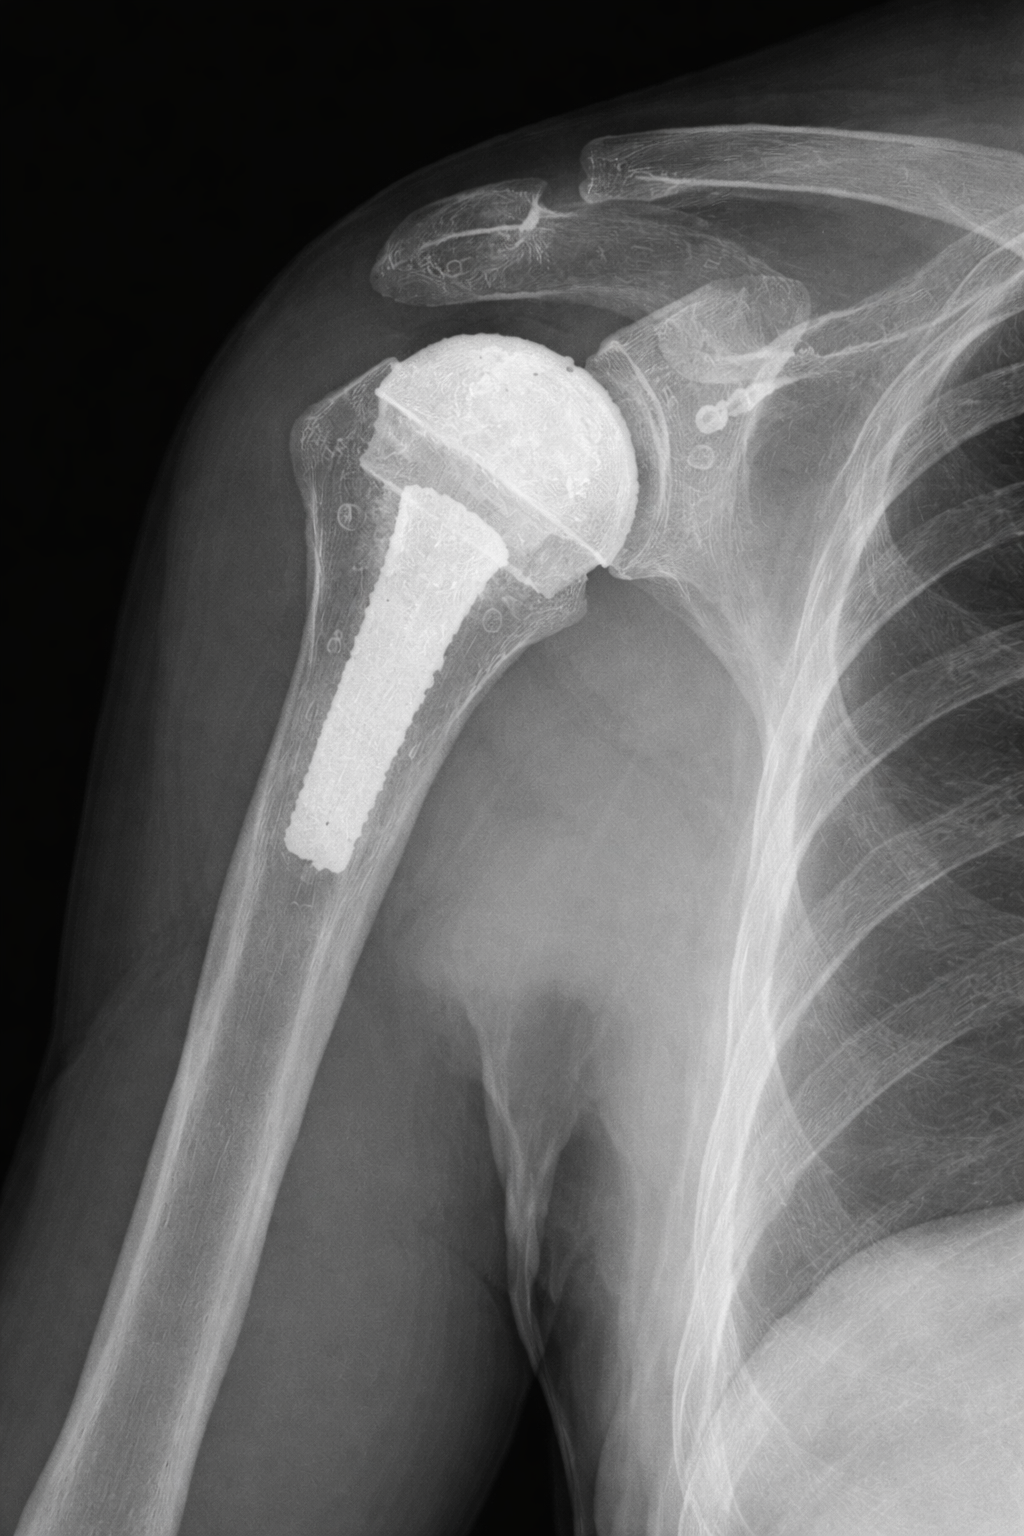

His practice has a primary focus on

shoulder replacement surgery, including anatomic and reverse total shoulder arthroplasty.

Shoulder Arthritis